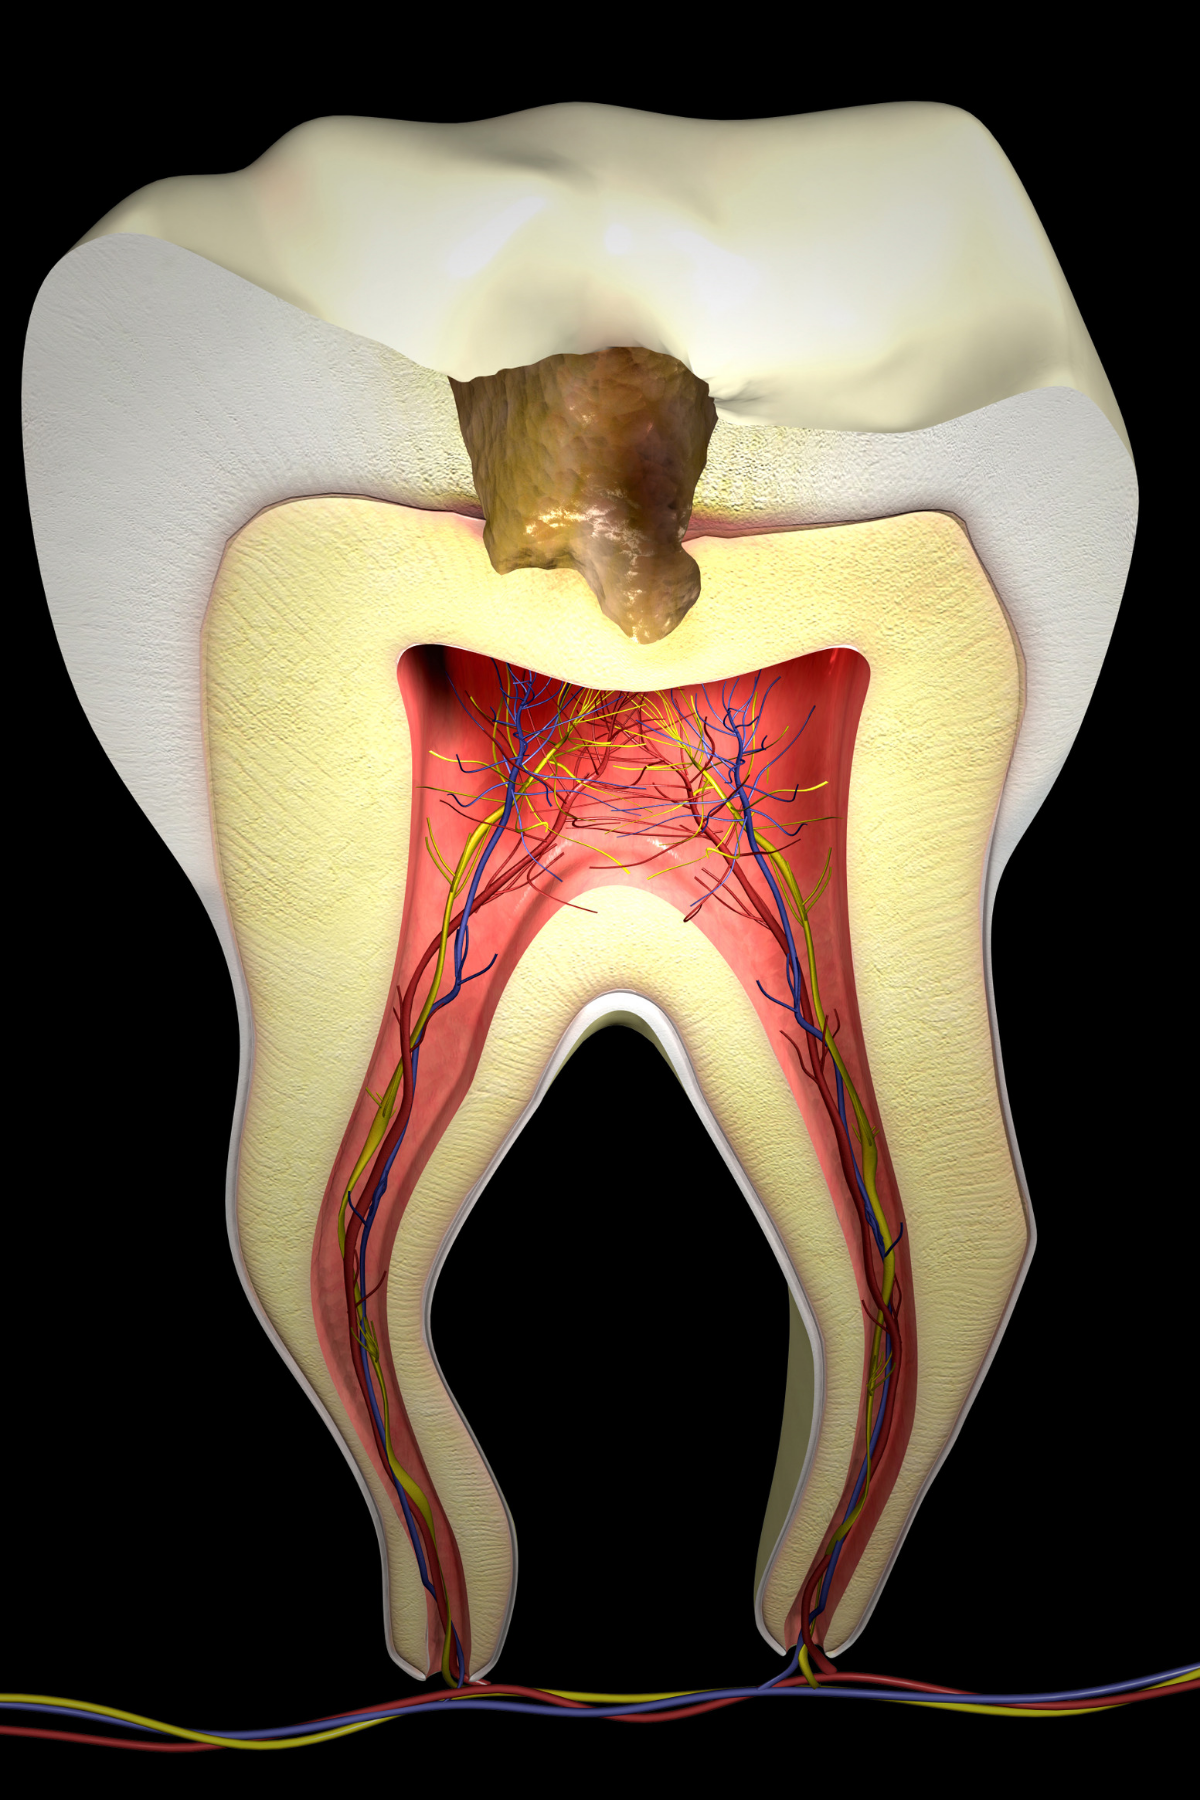

Root Canal Treatment

Root Canal Treatment is a procedure performed on the infected tooth to remove the decay affecting the pulp (underlying tissue containing blood vessels and nerve supply to a tooth). Simple filling procedure cannot restore a tooth’s dental health when the infection has encroached the pulp. Root canal therapy is the only alternative to save such tooth from being extracted. The main objective of root canal treatment is to preserve the infected existing natural tooth by disinfection. During a root canal therapy, access to the root canal present inside the root of a tooth is gained and the infected tissue is removed entirely. Hence Root Canal treatment bypasses extraction of the infected tooth and its replacement procedures thereby saving time and money.